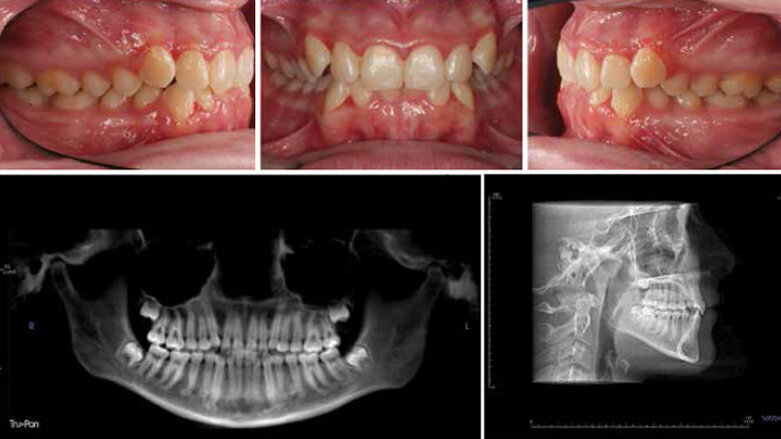

Fig. 1: Initial records. (Photos: Michael J. Mayhew, DDS, MS, MS, & Nicole R. Scheffler, DDS, MS)

Fig. 1 shows the initial records of a case with narrow arches, malalignment, deep bite treated with the Damon Ultima System. Fig. 2 demonstrates the alignment achieved with a 0.014 x 0.0275 CuNiTi Combee wire. The round-sided rectangular Damon Ultima wire engagement at the horizontal contact points delivered efficient rotation control and angulation alignments resolved earlier because of improved wire bracket interface along the vertical contacts. Fig. 3 reveals final alignment compared for this case completed in 14 months.